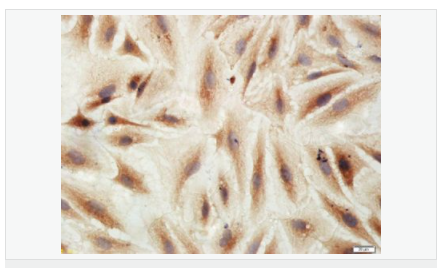

| 產(chǎn)品應(yīng)用 | WB=1:500-2000 IHC-P=1:100-500 IHC-F=1:100-500 Flow-Cyt=3ug/test ICC=1:100-500 IF=1:100-500 (石蠟切片需做抗原修復) not yet tested in other applications. optimal dilutions/concentrations should be determined by the end user. |

| 產(chǎn)品介紹 | This gene encodes an adenosine receptor that is a member of the G protein-coupled receptor superfamily. This integral membrane protein stimulates adenylate cyclase activity in the presence of adenosine. This protein also interacts with netrin-1, which is involved in axon elongation. The gene is located near the Smith-Magenis syndrome region on chromosome 17. [provided by RefSeq, Jul 2008]. Function: Receptor for adenosine. The activity of this receptor is mediated by G proteins which activate adenylyl cyclase. Subcellular Location: Cell membrane; Multi-pass membrane protein. Similarity: Belongs to the G-protein coupled receptor 1 family. SWISS: P29275 Gene ID: 136 Database links: Entrez Gene: 136 Human Omim: 600446 Human SwissProt: P29275 Human Unigene: 167046 Human Important Note: This product as supplied is intended for research use only, not for use in human, therapeutic or diagnostic applications. |